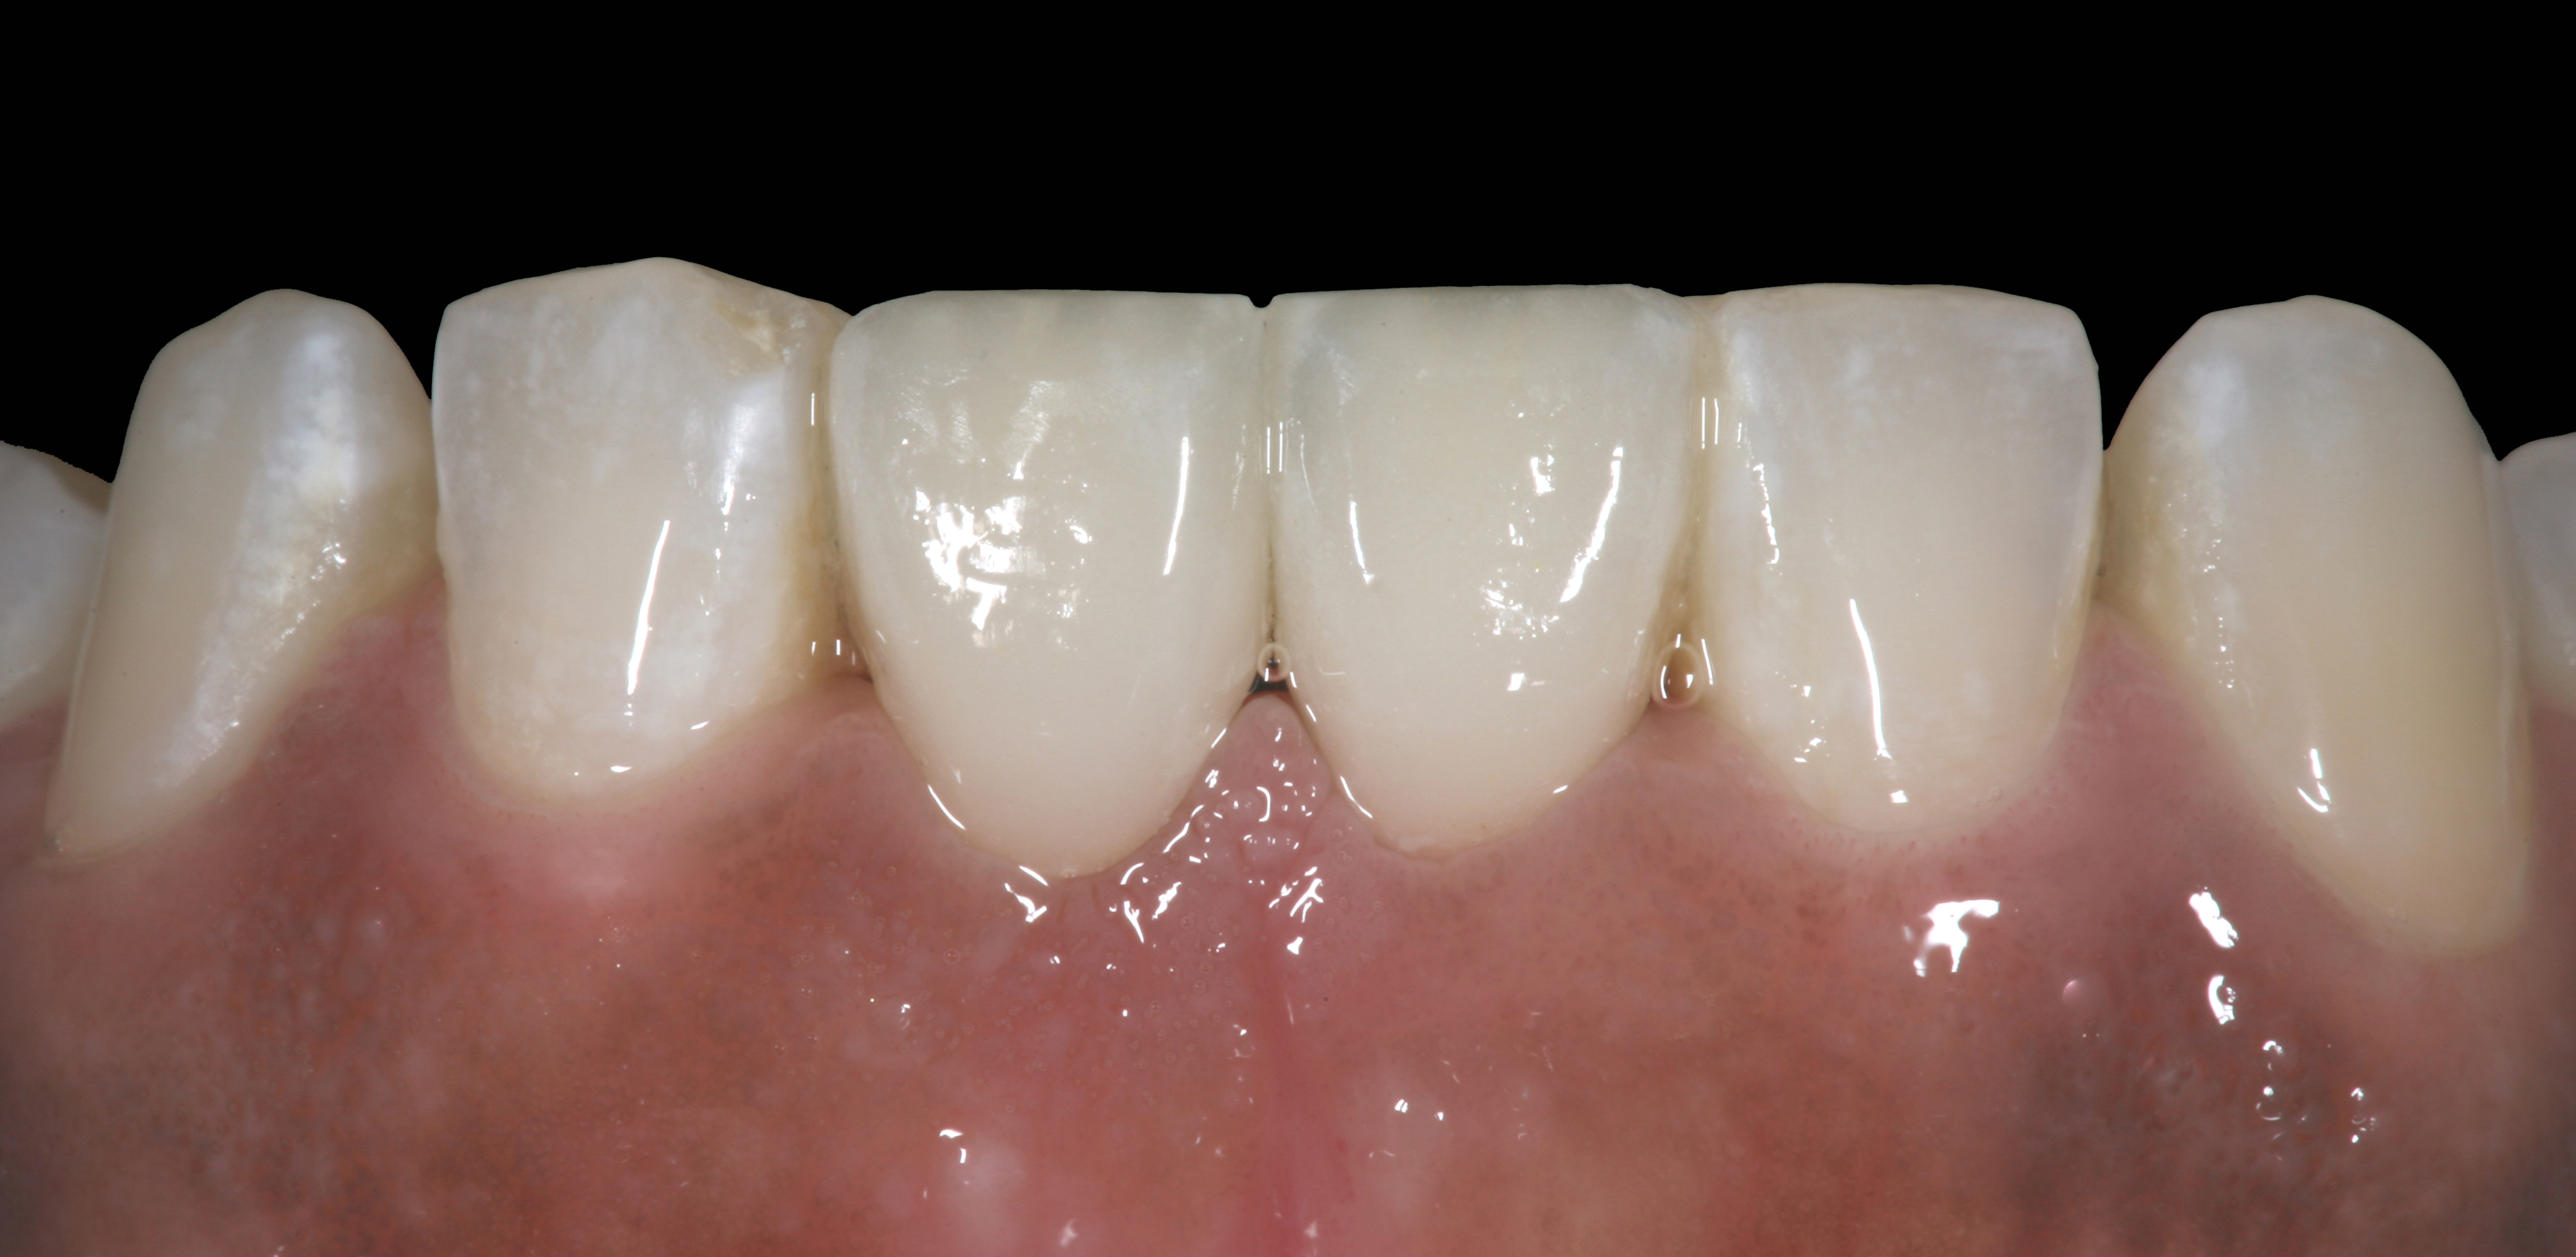

The pretreatment situation.

Figure 13